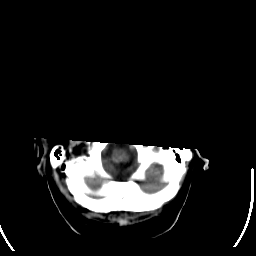

Stroke CT #2 -- Slice #1

[Home][Help][Clinical] Slice 1